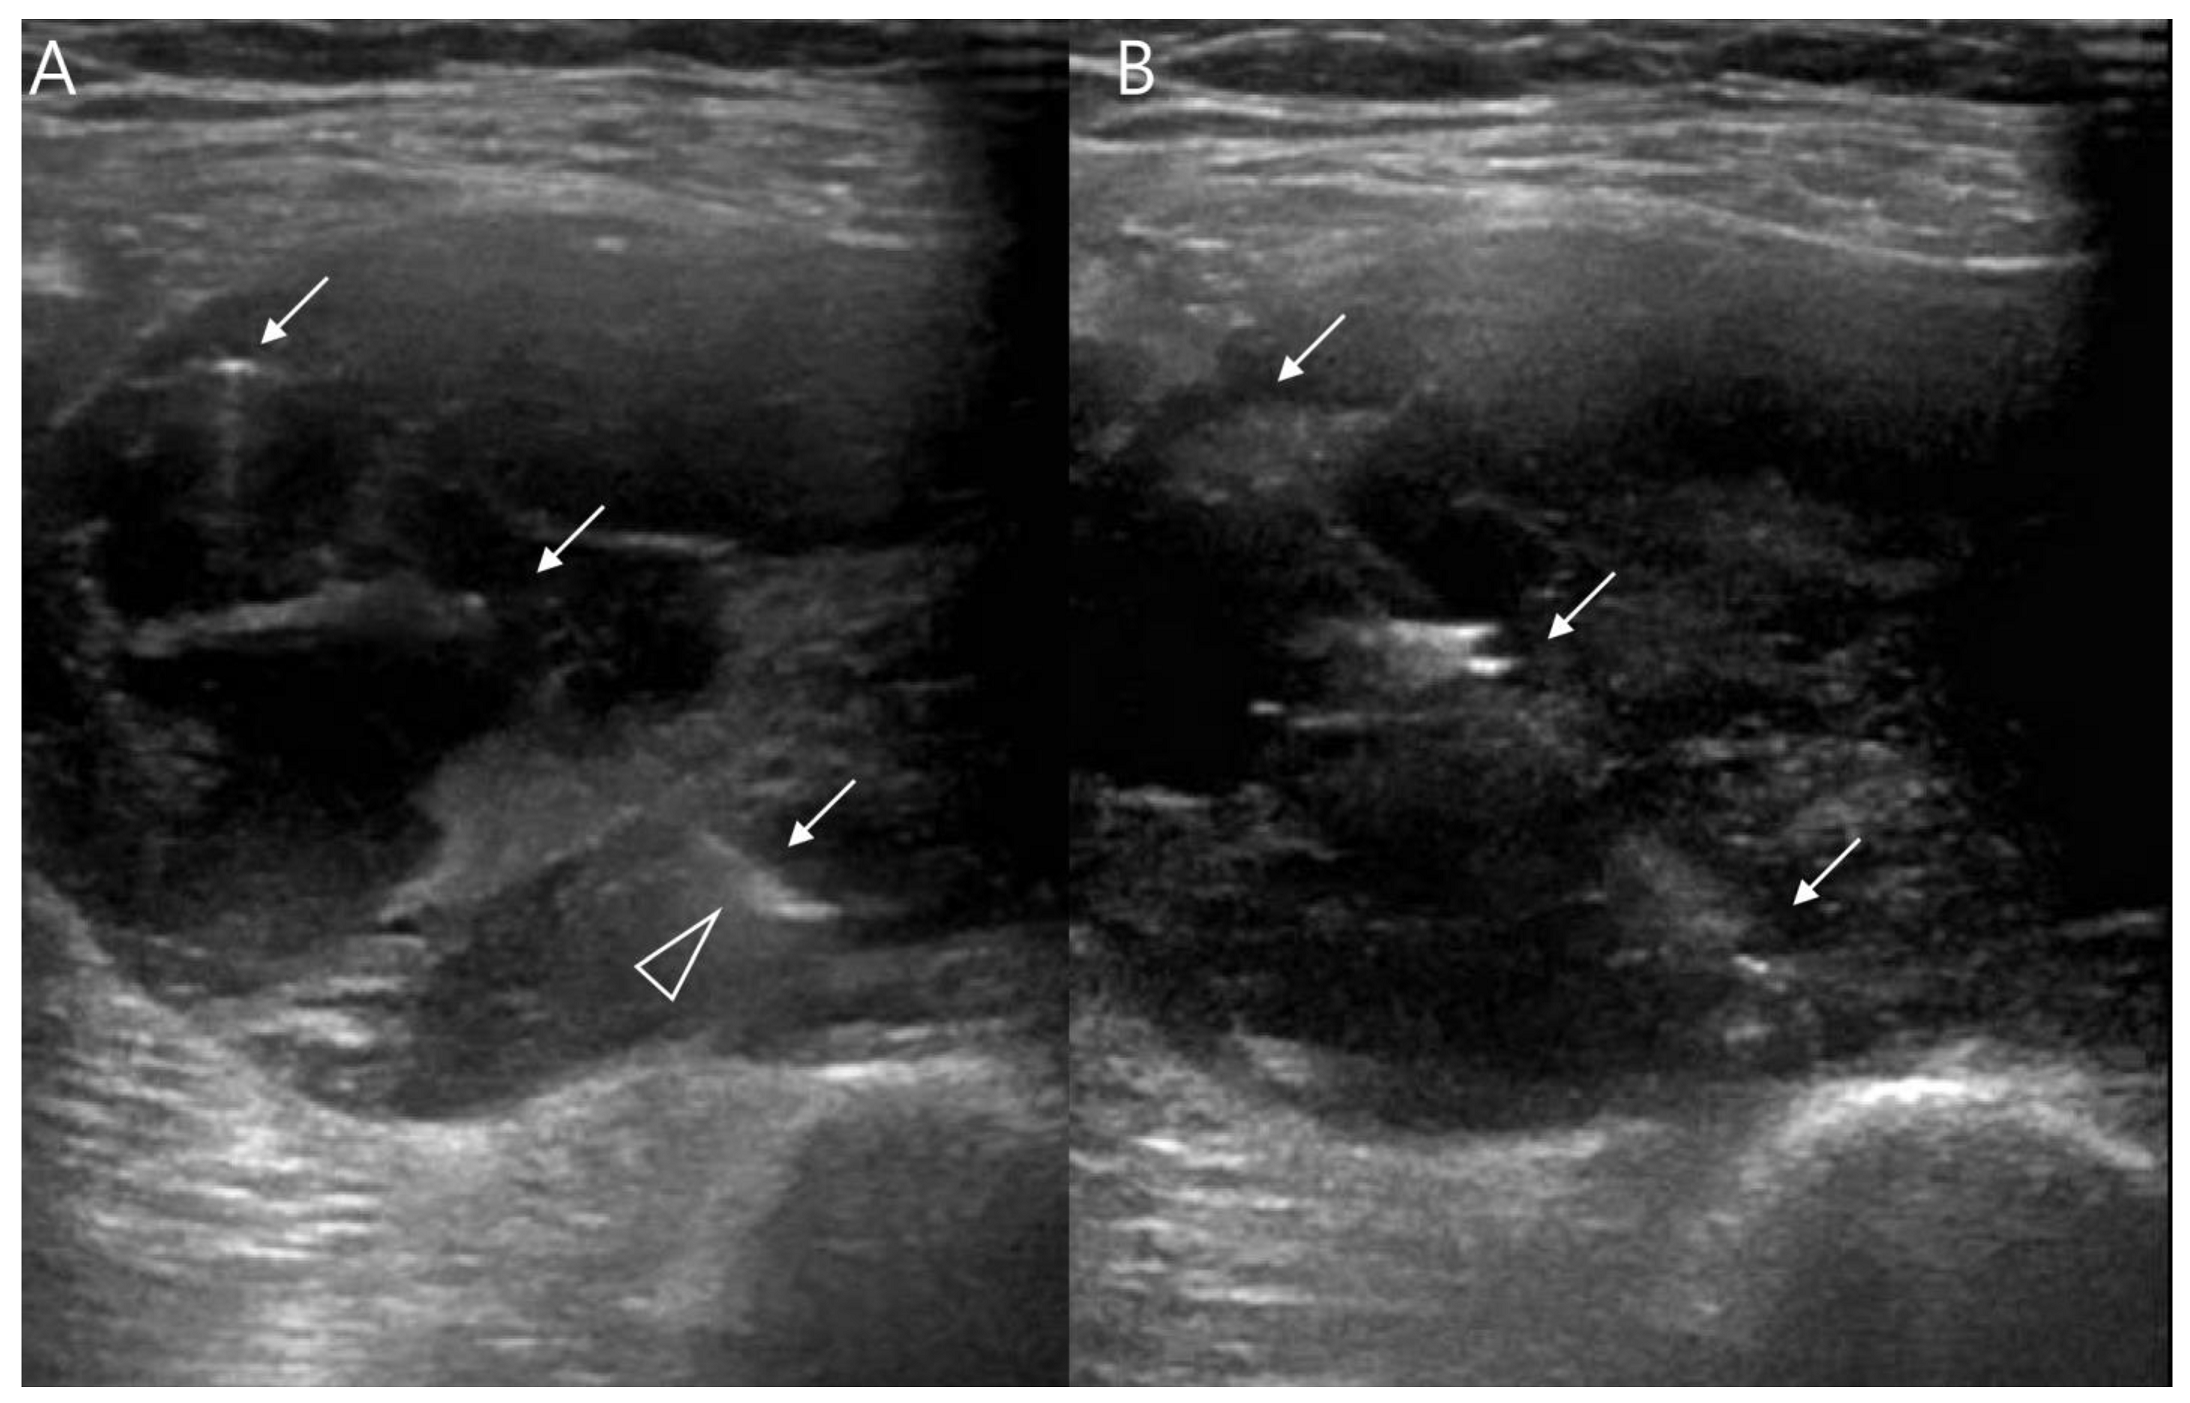

2.3. Ultrasound

3. Uncommon Primary Sites of Synovial Sarcoma in the Extremities